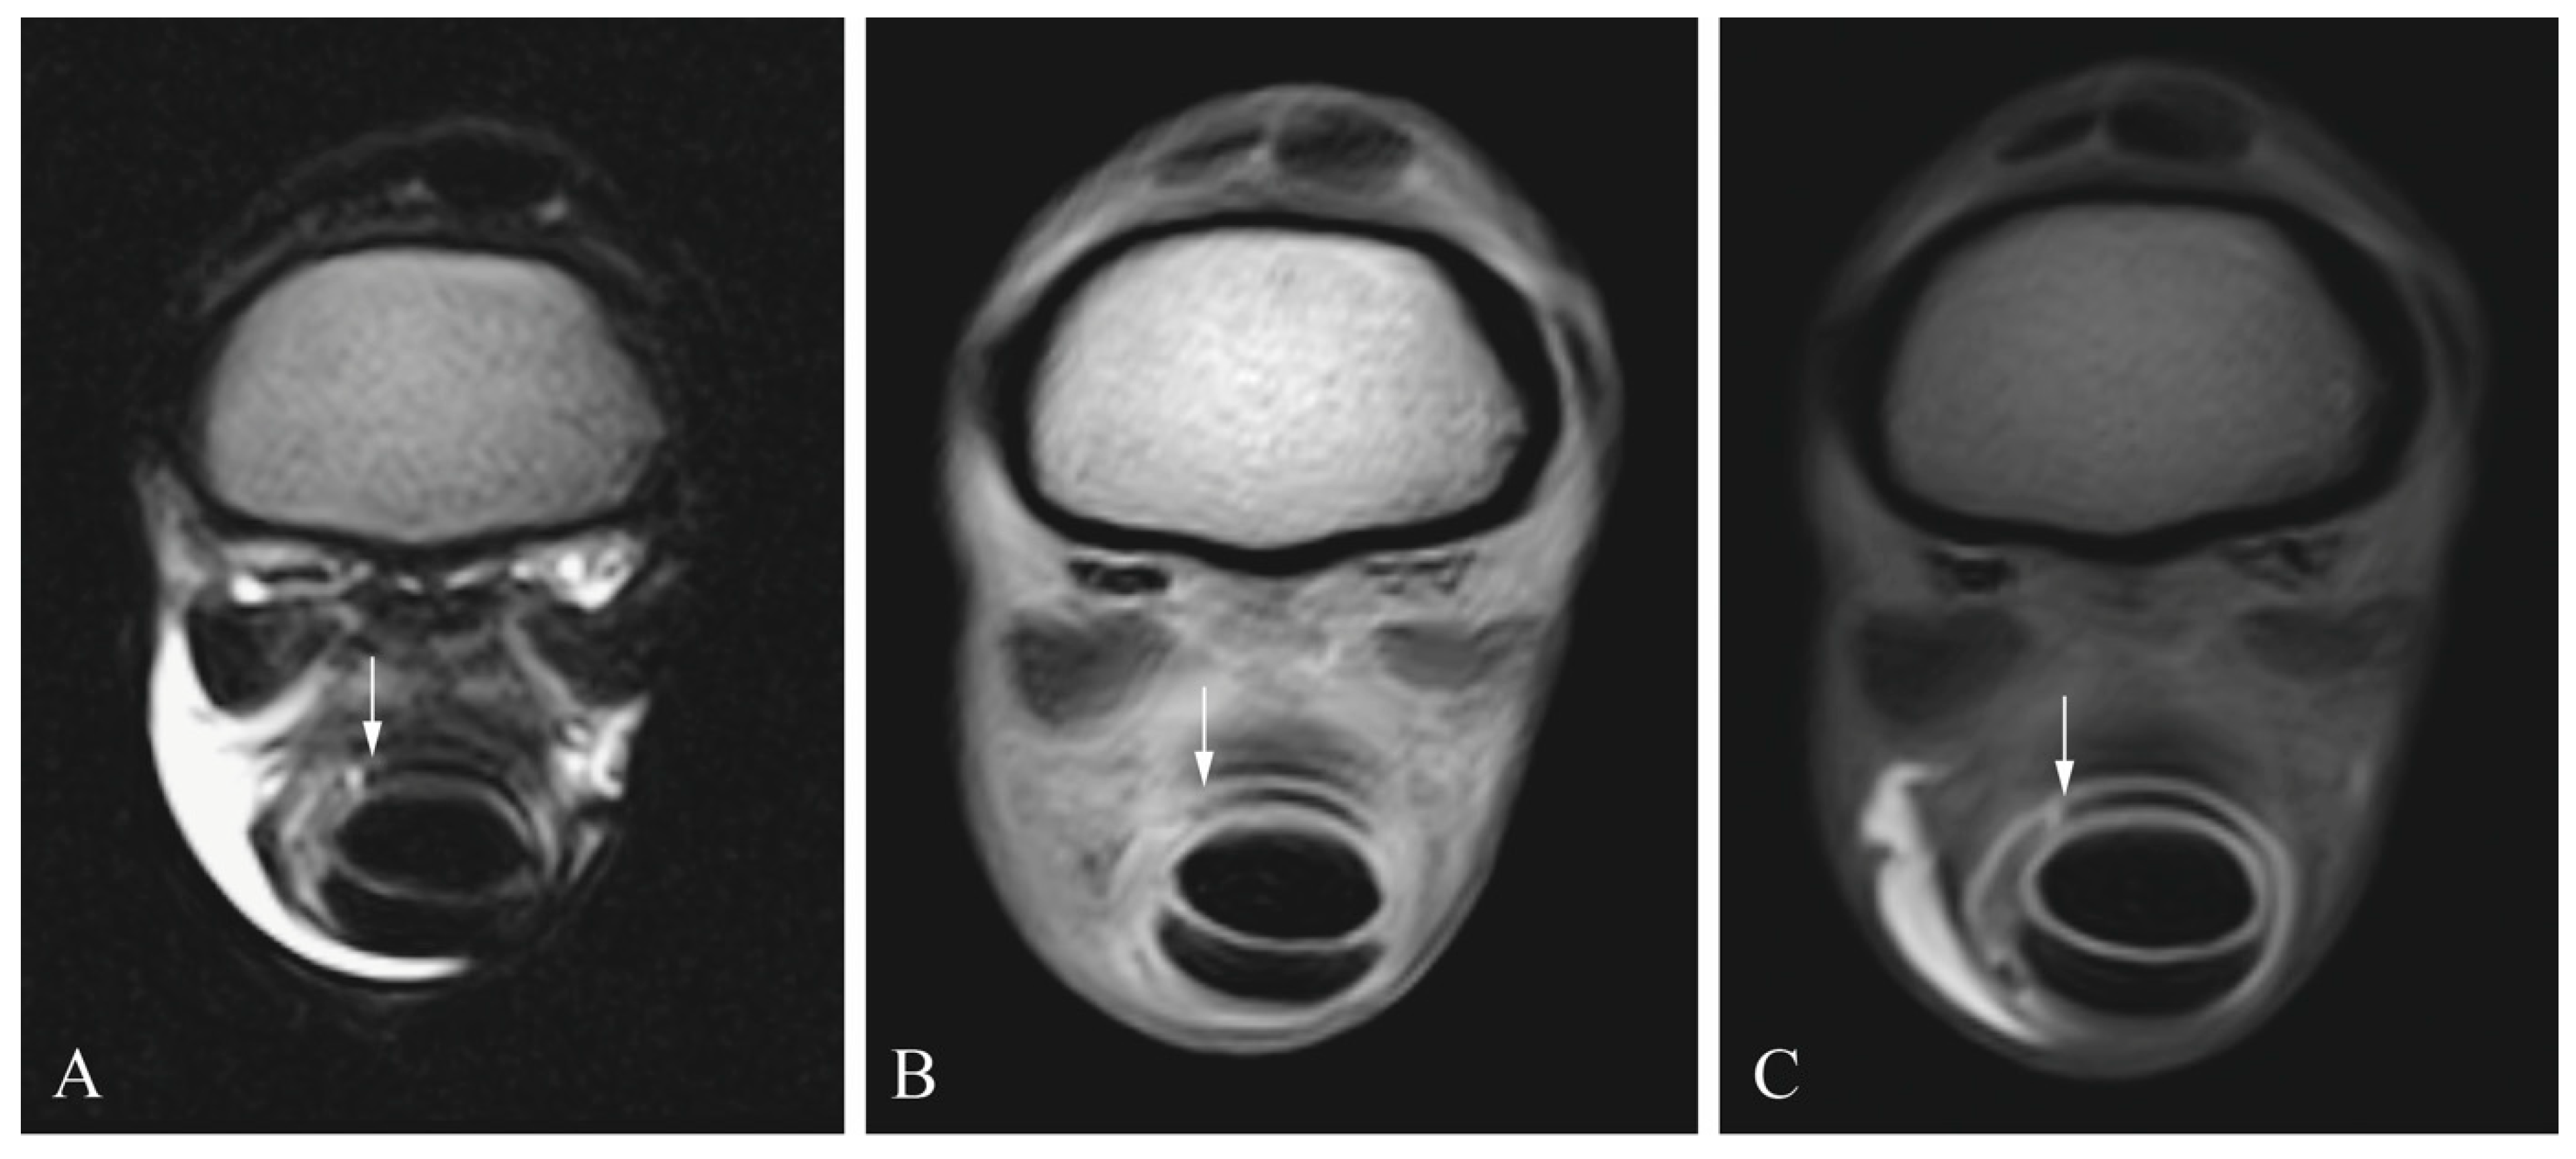

2.2. Tenoscopic Procedure

2.3. Diagnostic Imaging

2.4. Image Analysis